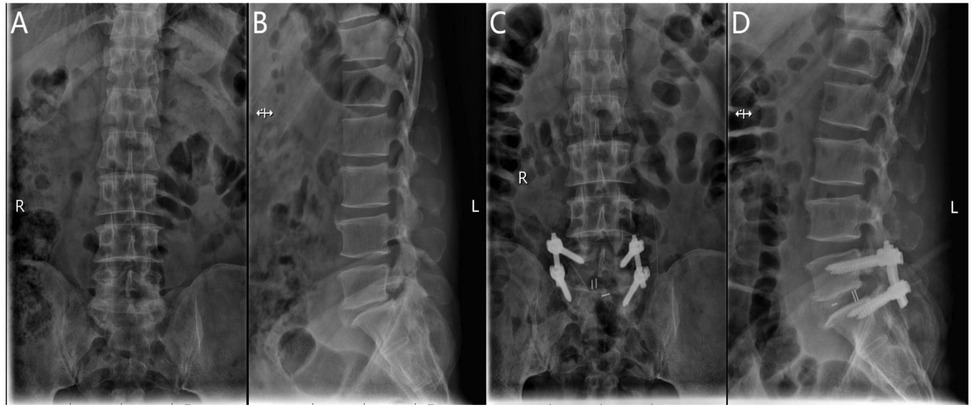

After general anesthesia, the patient is positioned prone with the abdomen suspended and slight flexion of the lumbar spine. The C-arm x-ray machine is used to identify the responsible intervertebral space and confirm the spinous processes, pedicles, and transverse processes of the affected segment. The location of the endoscope and working channel is determined at the intersection of the lower horizontal extension line of the caudal lamina and the vertical bisector of the upper pedicle of the adjacent vertebra, 1.0 cm above and below the intersection. Routine disinfection is performed, and the surgical site is draped. Under C-arm fluoroscopic guidance, the pedicle screw guidewire is inserted and left in place, while the endoscope, radiofrequency electrode knife, drill, and irrigation system are connected. The skin and deep fascia are incised step by step, and the dilating catheter is introduced to the multifidus muscle triangle for initial soft tissue dissection. The UBE dissector is then used for further dissection. The UBE endoscope is introduced into the working channel, and instruments are inserted under endoscopic monitoring. The operative channel may be exchanged as needed. Initially, unilateral or bilateral decompression of the spinal canal is performed under endoscopic guidance by removing the inferior lamina and part of the superior articular process of the affected vertebra. The outer bony wall of the superior articular process is preserved as much as possible to protect the nerve root exit. The resected bone is used for intervertebral grafting. The ligamentum flavum is removed to expose the dura mater, nerve root exit, and walking root. Under nerve root protection, the opposite side is retracted using a sheath, and instruments such as the nucleus forceps and rongeurs are used to remove the intervertebral disc tissue and scrape the cartilage endplate to expose the bony endplate. The trial fusion device is then placed into the intervertebral space to determine its size. Interbody grafting is performed, and an appropriately sized intervertebral fusion device is inserted. After placing the fusion device, pedicle screws are inserted along the guidewire. C-arm fluoroscopy is used to confirm the correct positioning of the screws, and the bilateral connecting rods are installed vertically and tightened. A final C-arm fluoroscopic check ensures the proper placement of the internal fixation device and the intervertebral fusion device. The surgical wound is sutured, and sterile dressings are applied (Figure 3).

Figure 3. (A) Preoperative anteroposterior radiograph of the lumbar spine; (B) preoperative lateral radiograph of the lumbar spine; (C) postoperative lateral radiograph showing spinal instrumentation; (D) postoperative anteroposterior radiograph showing spinal instrumentation.